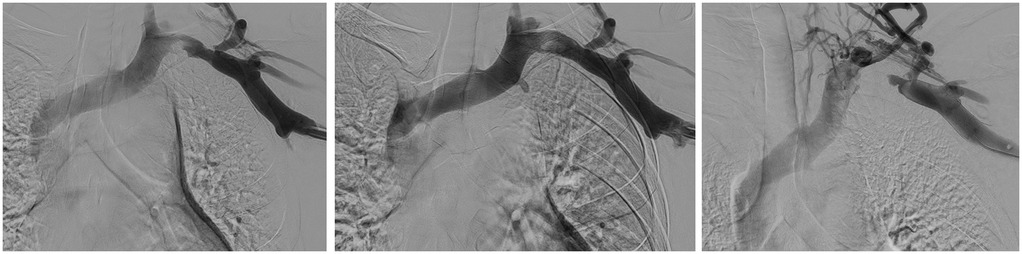

Effort thrombosis, also known as Paget-Schroetter Syndrome, is a rare venous manifestation of Thoracic Outlet Syndrome, primarily affecting young adults who perform repetitive overhead motions, such as athletes and trades workers. Stasis occurs when surrounding tissues encroach upon venous flow through the subclavian and/or axillary veins, manifesting as pain, swelling, and discoloration, with a potential for pulmonary embolism and other sequelae if left untreated. We present a 22-year-old male, avid weightlifter, with initial and recurrent left subclavian thrombosis and right pulmonary emboli, who did not respond to mechanical thrombectomy and anticoagulation, requiring surgical reconstruction at the thoracic outlet only two weeks after initial presentation. While there are no consensus guidelines for the management of Paget-Schroetter syndrome, aggressive management of acute thrombi demonstrates low rates of recurrence. There is less guidance regarding subacute thrombi. We advocate for a similarly aggressive approach to management of subacute thrombi to prevent recurrence and complications such as pulmonary embolism, post-thrombotic syndrome, and vessel fibrosis.